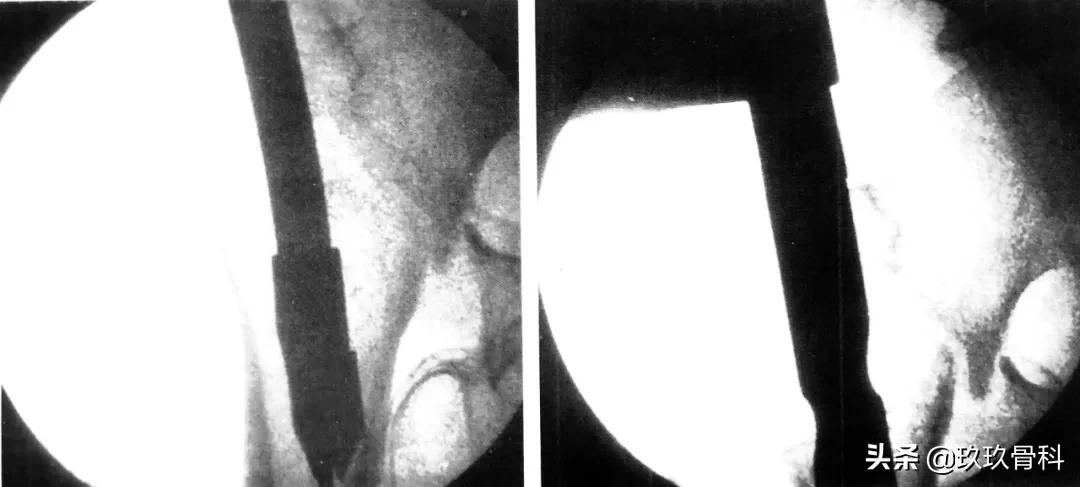

C 形臂下操作步骤,尖端开髓、插入导针

骨科取髓内钉的视频,骨科髓内钉内固定术式简写

扩髓、主钉置入

正位拉力钉导针位置、侧位拉力钉导针位置